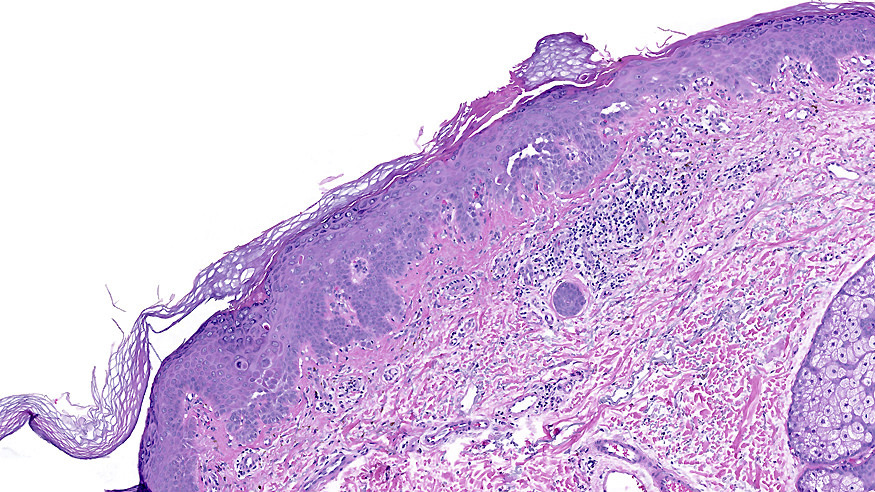

Microscopic (histologic) description

- Suprabasal acantholysis with vesicle formation is the principal microscopic finding

- Elongation of rete ridges with focal acantholysis and eosinophils may be the only early changes in Grover disease

- Main 4 histopathological patterns are:

- Darier-like: suprabasal acantholysis of keratinocytes with scattered apoptotic or dyskeratotic cells within various levels of the epidermis

- More than one pattern can be seen in the same setting

- Other newly described histopathological pattern include: (Am J Dermatopathol 2010;32:541)

- Lentiginous: elongation of the rete ridges with some basal hyperpigmentation resembling a solar lentigo or Dowling-Degos disease

Microscopic (histologic) images